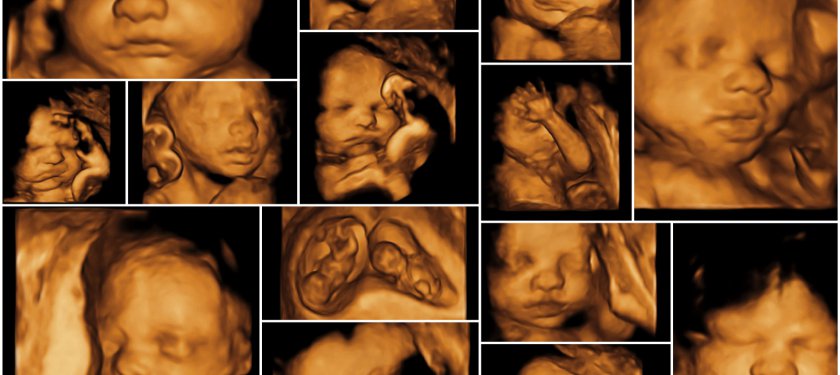

Geleneksel 2D ultrasonlarda ses yansımaları düz olarak gelirken, 3D ultrasonlarda belirli açılarla olmakta ve böylelikle dokular ayrıntılı bir şekilde görüntülenebilmektedir. 3 boyutlu ultrasona zaman boyutu eklendiğinde, işte bu noktada 4 Boyutlu Ultrason adını almaktadır. 3 boyutlu ultrasonda bebeğin hareketleri gecikmeli olarak gözlenirken yeni 4 boyut teknolojisi sayesinde bebeğin hareketleri aynı anda görülebilmektedir. 4 boyutlu ultrasonda bebeğinizin hareketlerini, gülümsemesini, , parmağını emmesini, dilini çıkarmasını veya esnemesini aynı zamanda görebilirsiniz. İlk defa bebeğini 4D ultrasonda gören anne ve baba adayları bu görüntüden çok etkilenmektedirler. 4 boyutlu görüntüler üzerinden rahatlıkla bebeğin kime benzediği hakkında fikir bile yürütülebilir. Çünkü 4 boyutlu ultrason bebeğin cildini gösterir, o yüzden gerçeğe yakın görüntüler elde edilir. Oysa 2 boyutlu ultrason görüntüsü siyah-beyazdır, bulanıktır. Bebeğin iç organlarını gösterir, cildini göstermez. Dolayısıyla alınan görüntüler hastaları tatmin etmeyebilir.

4D ultrasonda iyi görüntü alabilmek için bazı kriterler gerekir. Öncelikle bebeğin yüzünün görüntü açısına dönük olması gerekir. Ayrıca bebeğin yüzü ile rahim duvarı arasında yeterli miktarda sıvının olması gerekmektedir. Eğer bebeğin yüzü arkaya dönükse, başı aşağı inmişse veya suyu yeterli değilse net görüntü alınamaz. Bu durumlarda net görüntü alabilmek için sizden sağa veya sola dönmeniz istenebilir. Ya da biraz dolaştıktan sonra veya tatlı bir şeyler yedikten sonra 4 Boyutlu Ultrason tekrarlanabilir. 4D ultrason hizmeti almak isteyen anne ve baba adaylarının en çok sorduğu sorulardan biri de 4 boyutlu ultrasonun ne zaman yapılacağıdır. Bebeği 4 boyutlu ultrasonla sağlıklı ve net bir şekilde görüntülemek için en iyi haftalar gebeliğin 26-30. haftaları arasıdır. 26 haftanın altında bebeğin cilt altı yağ dokusu az olduğu için güzel görüntü alınamaz. 30. haftadan sonra da bebeğin yeri daraldığı ve pelvise doğru indiği için net görüntü alınamayabilir. Bu süreçler hakkında doğru bilgiye sahip olarak uygulamaya dahil olmanız daha sağlıklı olacaktır.